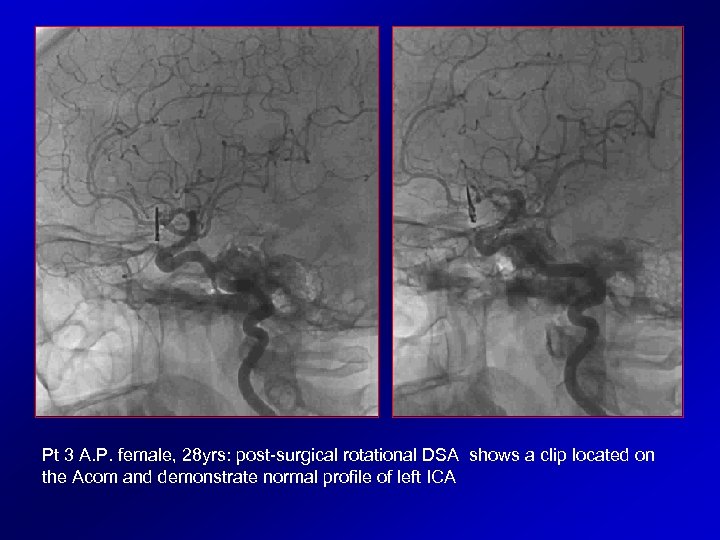

Pt 3 A. P. female, 28 yrs: post-surgical rotational DSA shows a clip located on the Acom and demonstrate normal profile of left ICA